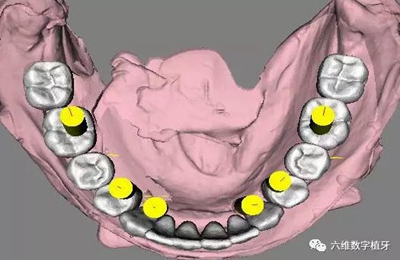

治療計劃及種植方案設(shè)計

1. 選擇適當(dāng)?shù)姆N植體尺寸,精確的避開前牙區(qū)骨壁較薄的地方。

2. 預(yù)先在軟件里面進(jìn)行排牙,根據(jù)最終修復(fù)的效果精確放置種植體的位置。

3. 充分評估患者的骨質(zhì)條件,手術(shù)之前事先將固定的臨時義齒做好,進(jìn)行即刻負(fù)重。